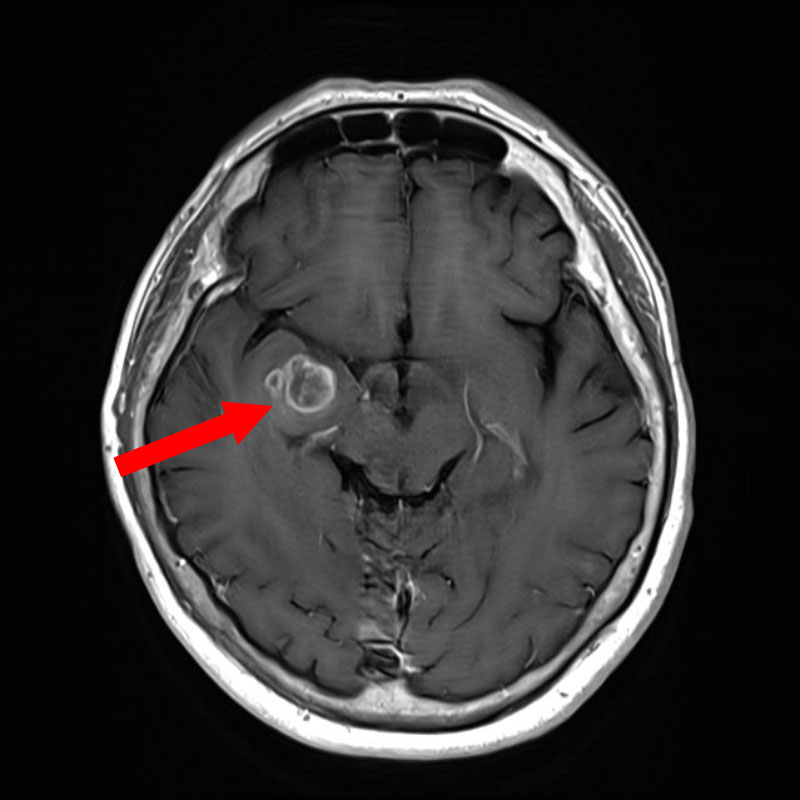

707

'25年12月

80代

髄膜腫

頭蓋内腫瘍摘出術

No.’25_109 手術前1

No.’25_109 手術前2